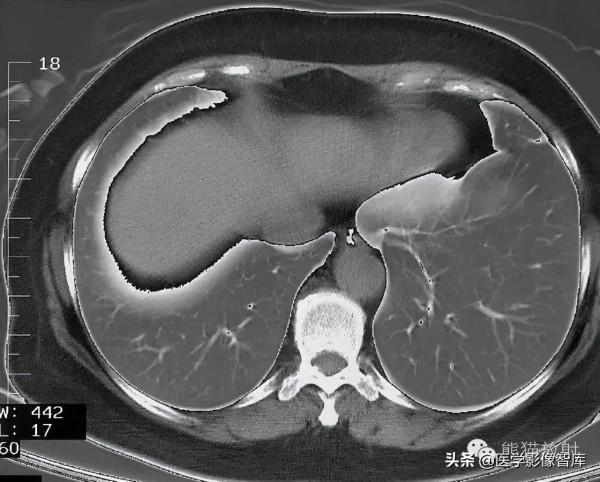

第十四層:肝靜脈水平

1. Intercostal muscle 肋間肌

2. Rib 肋骨

3. External oblique muscle 腹外肌

4. Right hepatic vein 肝右靜脈

5. Inferior vena cava 下腔靜脈

6. Left hepatic vein 肝左靜脈

7. Diaphragm 膈肌

8. Vagus nerve 迷走神經

9. Esophagus 食管

10. Liver (left lobe) 肝左葉

11. Rectus abdominis muscle 腹直肌

12. Stomach 胃

13. Left lung 左肺

14. Latissimus dorsi muscle 背闊肌

15. Liver (right lobe) 肝右葉

16. Right lung 右肺

17. Sympathetic trunk 交感幹

18. Erector spinae muscle 豎脊肌

19. Azygos vein 奇靜脈

20. Thoracic duct 胸導管

21. Spinal cord 脊髓

22. Thoracic vertebra 胸椎

23. Descending aorta 降主動脈

24. Posterior vagal trunk 迷走神經後幹

25. Spleen 脾臟